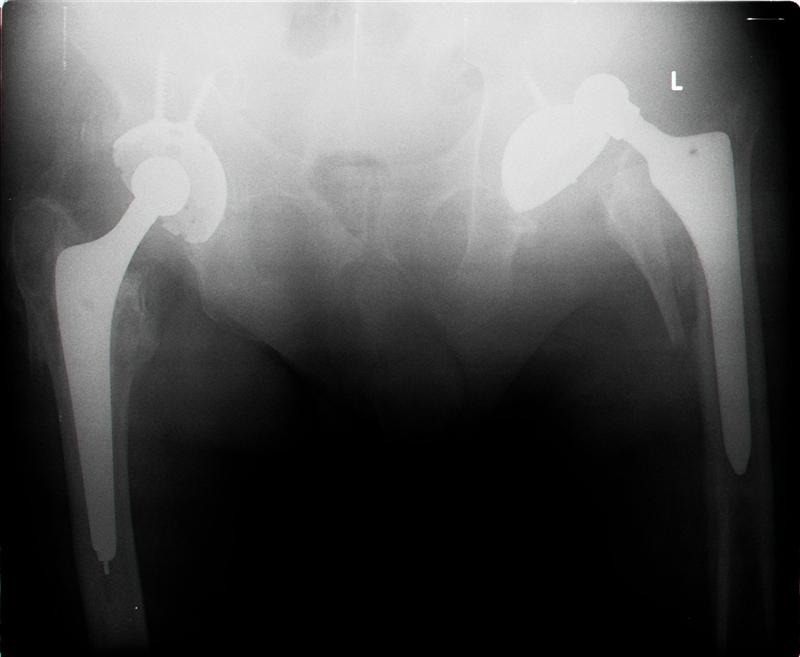

Patient 77 yaers old man falled two day after elective THR operation.

Was done noncemented THR,Direct Lateral Approuch .During posedure wasn't any complication.Now we have Vancouver AL fracture (to be more prosize between A to B1).What your sudgests?

Dear Sirs, in my opinion the actual problem isn't the AL fracture but the

hip dislocation.

The AL fracture can be well reduced and fixed with 2 cerclage wires and it is stable and heals, but why was there a dislocation? I see in fact an +

7mm neck so it means that the implant wasn't so stable at the end of surgery.

Good case - Problems are :

1. Dislocation - as it was through Lat approach abductor repair will also have failed

2. Fracture - In terms of classification doesn't fit neatly into Vancouver Classification because both lesser & greater trochanters are fractured - therefore is AL & AG.

Medial fracture line extends into diaphysis and would therefore be more accurately defined as a B fracture. The stem looks like a Zimmer proximally coated FMT therefore as it is only 2 days post-op & given the morphology of the fracture probably best described as a B2 fracture around loose stem.

Treatment - Revision surgery to include -

1. Stem revision to stem which allowed distal fixation - ie fully coated porous or tapered distal fixation stem.

2. Reduction of medial calcar fragment & greater

trochanter probably best achieved with rochanteric cable plate system

3. Regarding instability - offset was obviously an issue in primary surgery given long neck skirted head. Therefore I would advise careful intra-operative assessment of socket position and abductor damage. If component position poor then revisie socket if not increase head size to 36mm

(which will also lateralise liner helping offset) or if abductor damage significant consider constrained liner (the Trilogy socket that is in place will allow for both these options).